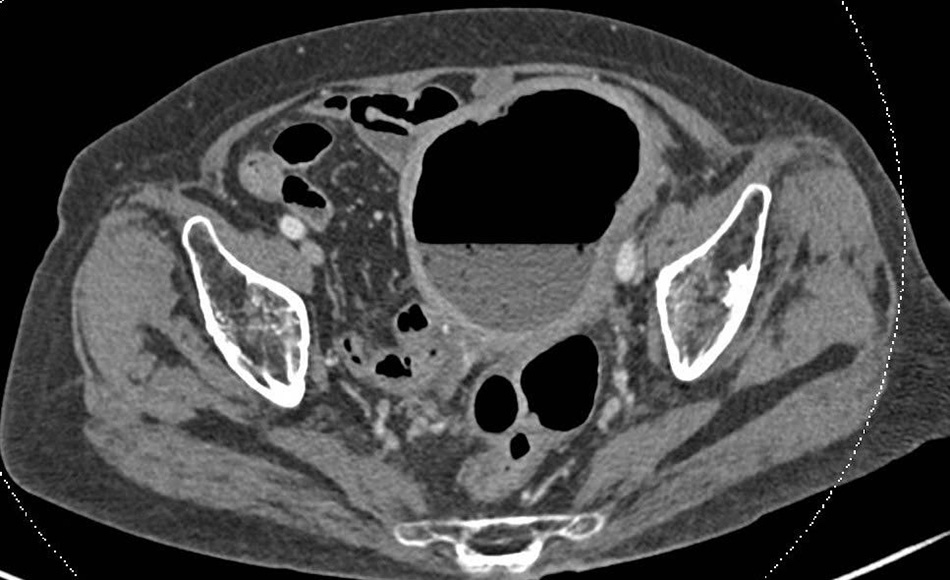

Mrs M.T.M., an 88-year-old patient from Ho Chi Minh City, was admitted to FV Hospital by her family in a condition marked by fever, persistent dull abdominal pain, and purulent vaginal discharge. Dr Le Duc Tuan, MSc, from the General Surgery Department, ordered a CT scan of the abdomen. Imaging revealed an abnormally enlarged uterus containing both fluid and gas.

The CT scan revealed an abnormally enlarged uterus containing a significant amount of gas and fluid.